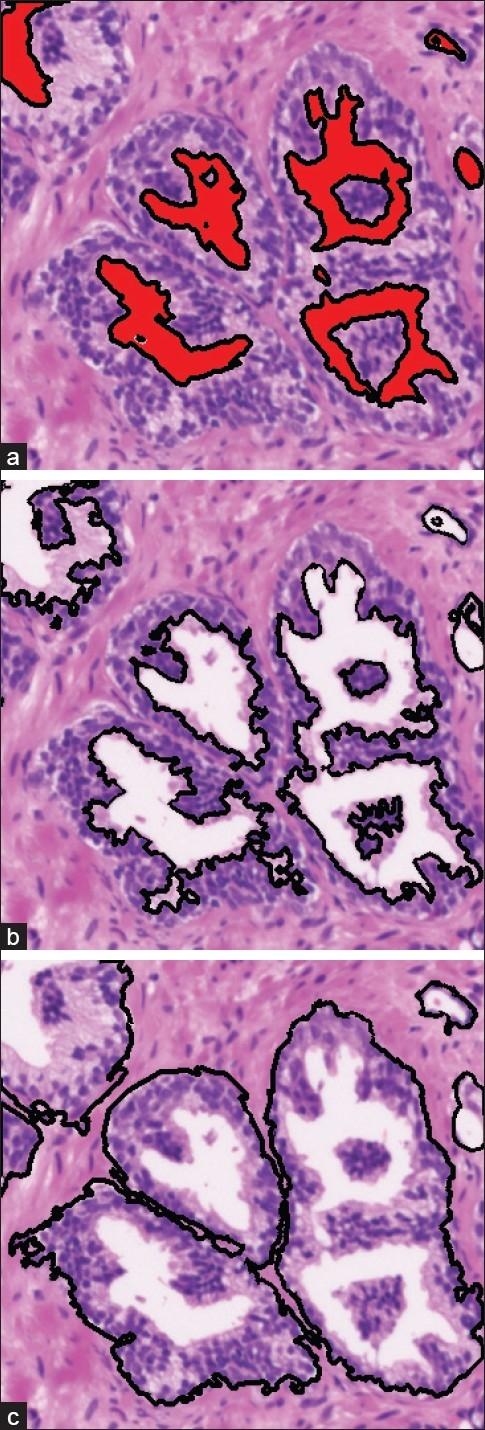

With modern automated microscopes and digital cameras, pathologists no longer have to examine samples looking through microscope binoculars. Instead, the slide is digitized to an image, which can then be examined on a screen. This creates the possibility for computers to analyze the image. In this work, a fully automated approach to region of interest (ROI) segmentation in prostate biopsy images is proposed. This will allow the pathologists to focus on the most important areas of the image. The method proposed is based on level-set and mean filtering techniques for lumen centered expansion and cell density localization respectively. The novelty of the technique lies in the ability to detect complete ROIs, where a ROI is composed by the conjunction of three different structures, that is, lumen, cytoplasm, and cells, as well as regions with a high density of cells. The method is capable of dealing with full biopsies digitized at different magnifications. In this paper, results are shown with a set of 100 H and E slides, digitized at 5×, and ranging from 12 MB to 500 MB. The tests carried out show an average specificity above 99% across the board and average sensitivities of 95% and 80%, respectively, for the lumen centered expansion and cell density localization. The algorithms were also tested with images at 10× magnification (up to 1228 MB) obtaining similar results.

借助现代自动化显微镜和数码相机,病理学家无需再通过显微镜双筒目镜来检查样本。取而代之的是,载玻片被数字化成图像,然后可以在屏幕上进行检查。这为计算机分析图像创造了可能性。在这项工作中,提出了一种用于前列腺活检图像中感兴趣区域(ROI)分割的全自动方法。这将使病理学家能够专注于图像中最重要的区域。所提出的方法分别基于水平集和均值滤波技术,用于以管腔为中心的扩展和细胞密度定位。该技术的新颖之处在于能够检测完整的ROI,其中一个ROI由三种不同结构的结合组成,即管腔、细胞质和细胞,以及细胞高密度区域。该方法能够处理以不同放大倍数数字化的完整活检样本。在本文中,展示了对一组100张苏木精和伊红(H&E)染色切片的结果,这些切片以5倍放大倍数数字化,大小从12MB到500MB不等。所进行的测试表明,总体平均特异性高于99%,以管腔为中心的扩展和细胞密度定位的平均敏感性分别为95%和80%。该算法还用10倍放大倍数的图像(高达1228MB)进行了测试,获得了相似的结果。